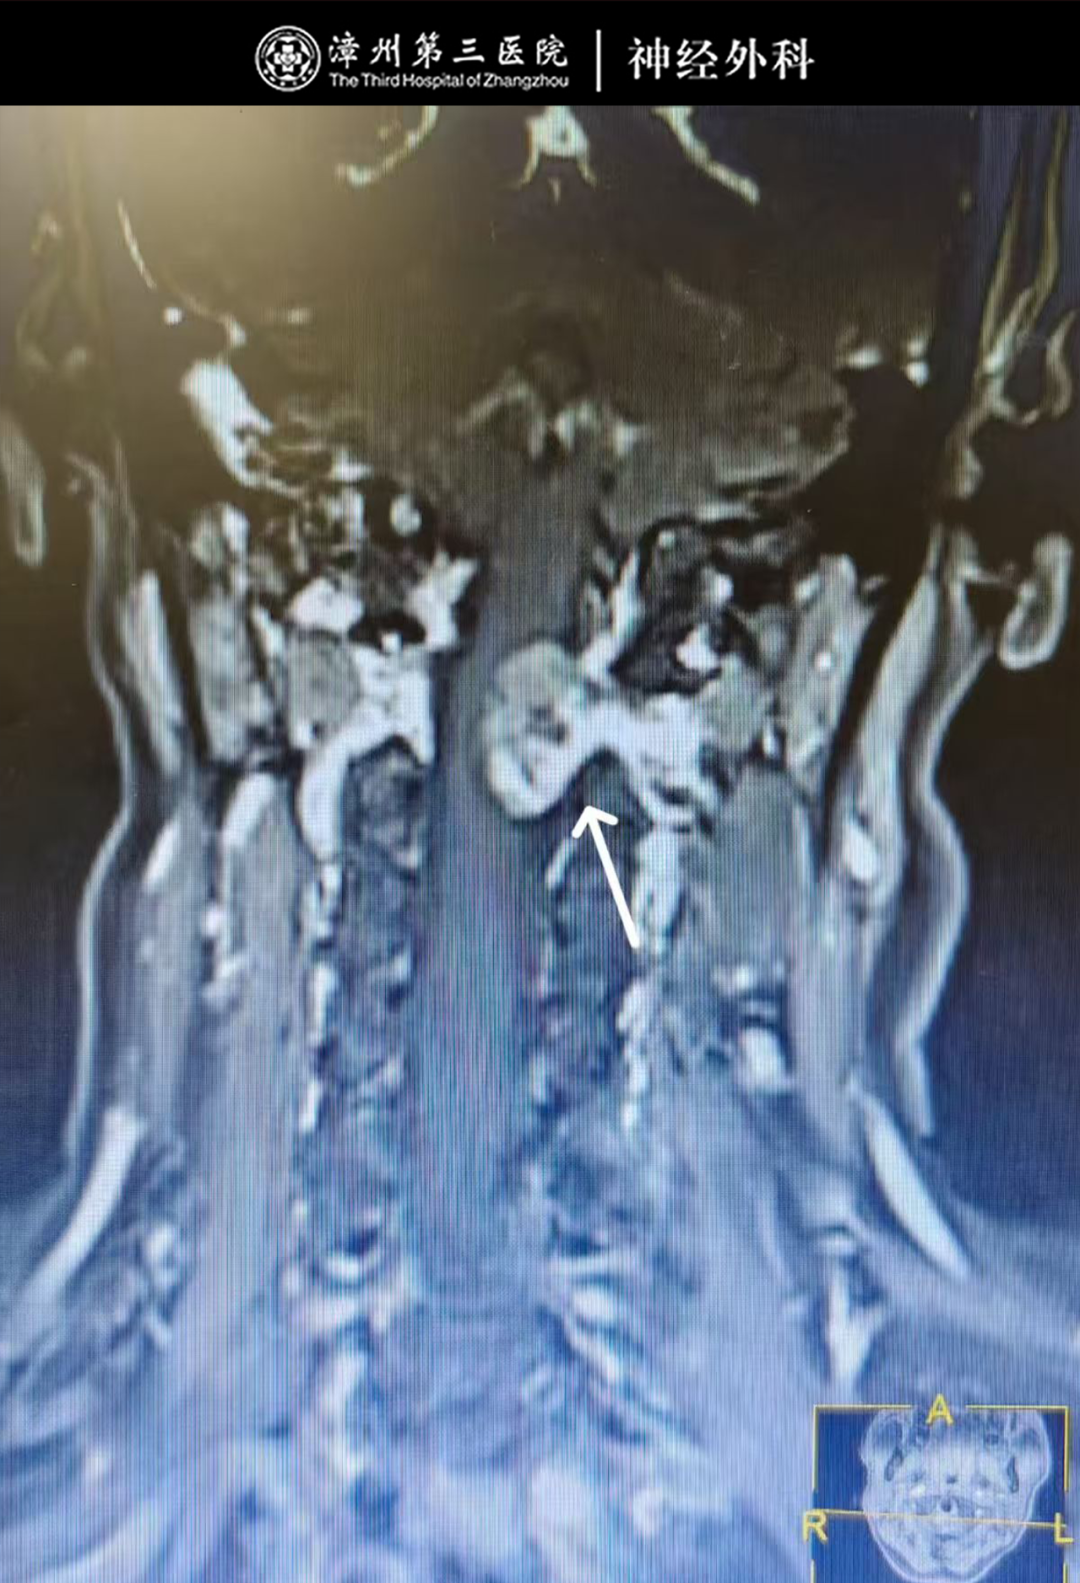

结合颈椎CT显示的C1-2椎体水平椎管内占位性病变特征、颈椎MR增强检查的精准定位,以及患者反复颈痛的临床症状,团队明确需手术切除占位组织以解除脊髓压迫、根除颈痛,且术后可通过病理检查明确占位性质,为康复提供依据。因手术部位邻近重要神经血管,难度与精度要求高,漳州第三医院副院长、神经外科专家林友城牵头制定“显微镜下C1-2硬膜下髓外占位切除术+神经根粘连松解术”个性化方案。